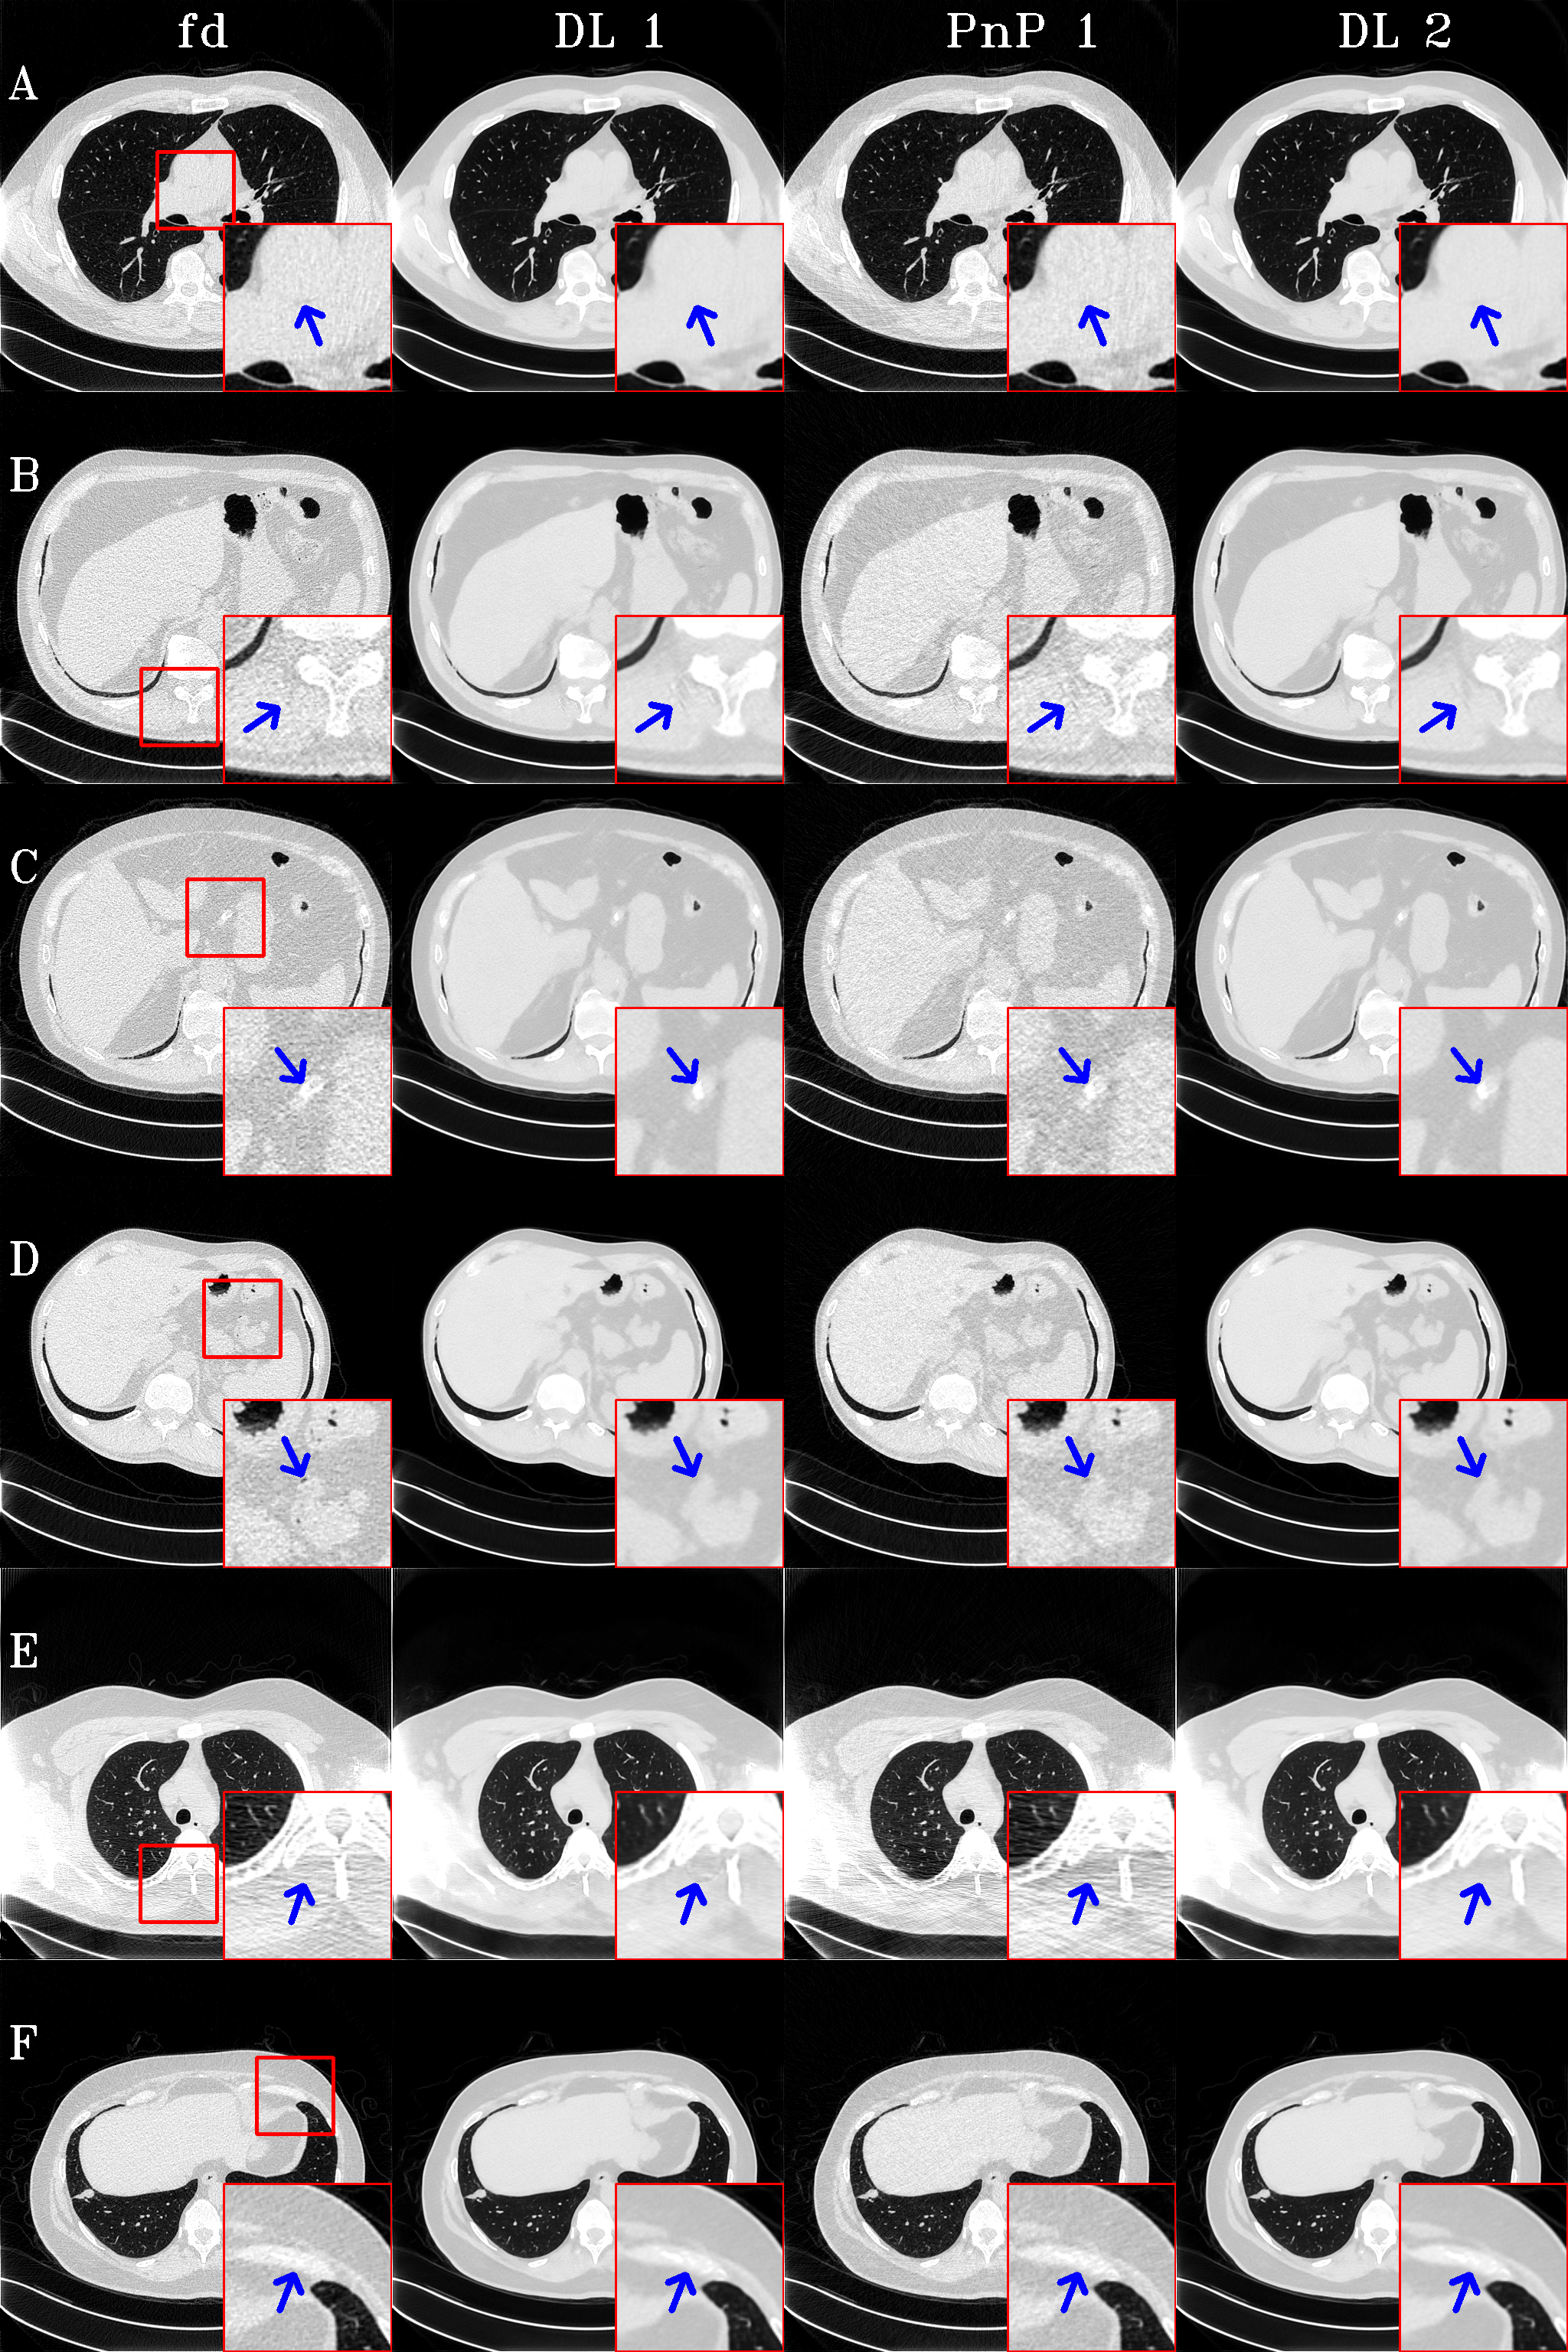

Fig. 7 provides evidence that the optimization process retrieved additional details from the sinograms, as indicated by the blue arrows. In this figure, the window is set to [-1000, 173] HU to include the muscle and bone areas.

Refer to caption

Fig. 7: Fine structures are better preserved by PnP, as illustrated by arrows.